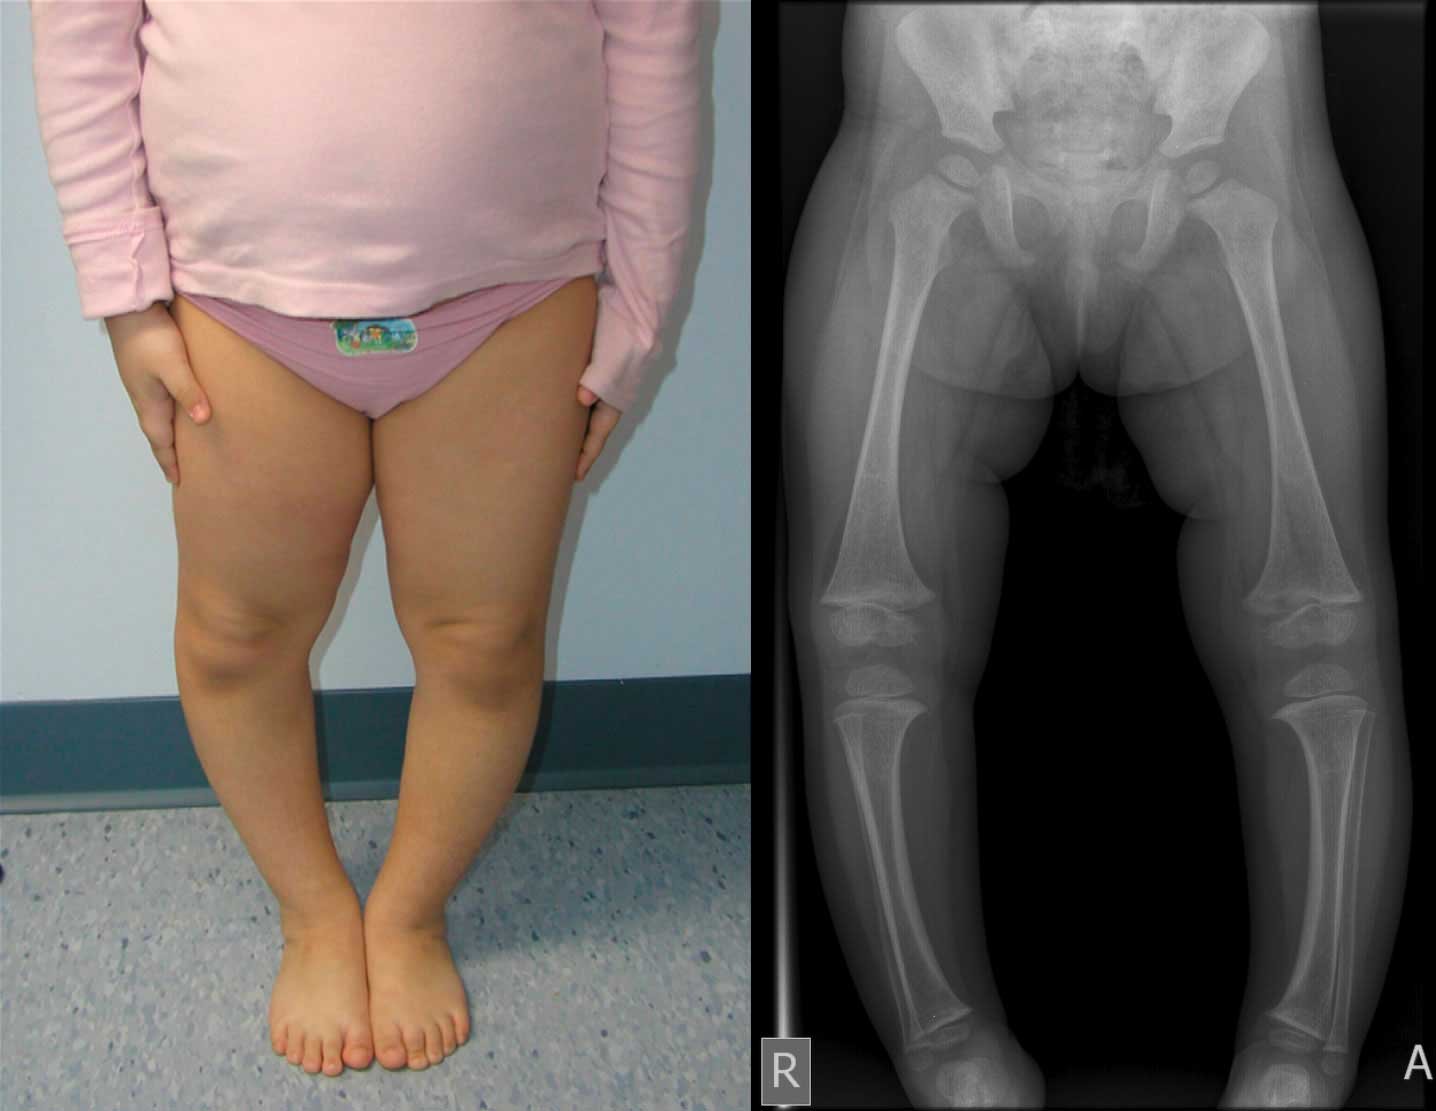

مرض بلاونت (Blount disease / Tibia vara) حالة مرضية تصيب الأطفال و خاصة المصابون بالبدانة منهم. و تبدأ أعراض هذا المرض فى السن من 2- 9 سنوات حيث يظهر تقوس فى الساق و يزداد هذا التقوس مع مرور الوقت. كما يصاحب هذا التقوس وجود إلتواء بالساق بحيث يكون إتجاه اصابع القدم الى الداخل و ليس الى الأمام. و هذا الإلتواء قد يؤدي الى كثرة سقوط الطفل أثناء المشي، وقد ينتج عنه ألم في الركبة بمرور الوقت.

سبب هذا المرض هو حدوث إضطراب فى مركز النمو الموجود بأعلى عظمة القصبة حيث يحدث بطء فى نمو الجزء الداخلي منه بينما يستمر النمو بصورة طبيعية فى الجهة الخارجية. و فى ثلثي المرضى يحدث هذا الإضطراب فى الساقين. و يجب أن يتم التفريق بين هذا المرض و بين تقوس الساقين الناتج عن نقص الكالسيوم و لين العظام حيث ان لكل منهما علاج مختلف.

- مكان التقوس: في مرض بلاونت يوجد التقوس أسفل الركبة مباشرة و ليس في منتصف الساق مثل فى حالة لين العظام

يتم تشخيص مرض بلاونت عن طريق الفحص البدني والأشعة السينية. في حالة الاشتباه في مرض بلاونت ، سيطلب دكتور جراحة عظام الأطفال إجراء أشعة سينية. قد تظهر الأشعة السينية تشوهًا في العظام وقد تظهر أيضًا تشوهات في لوحة النمو.